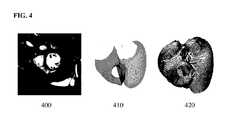

FIG. 4 illustrates exemplary results of generating a patient-specific anatomical heart model;

A model of fiber orientation can be automatically calculated based on the patient-specific geometry. In an advantageous implementation, the model of fiber orientation can be automatically calculated using a rule-based approach. A generic model of myocardium fiber architecture that includes fiber and fiber sheets is computed. A rule-based strategy is followed to generate the fiber architecture to cover the entire bi-ventricular myocardium from apex to valves. Below the basal plane, which is identified automatically using point correspondences of the initial triangulations of the anatomical model, the fiber elevation angle α, i.e. the angle with respect to the short axis plane, varies linearly across the myocardium, e.g., from −70 on the epicardium to +70 on the endocardium (values that can be defined by the user). Similarly, the sheet direction, which is defined by the angle β with respect to the outward transmural axis, varies transmurally, e.g., from +45 on the epicardium to −45 on the endocardium (values that can be defined by the user). α and β are computed for each point of the volumetric bi-ventricular myocardium mesh between the apex and basal plane based on the geodesic distance to the endocardia and epicardia identified by the facet tags: α=(depiαendo+dendoαepi)/(dendo+depi), where depi, dendo, αepi, and αendoare the distances and angles at the endocardium and epicardium, respectively. The fiber and sheet orientations are then fixed around each valve. In particular, fibers are longitudinal around the aortic valve and tangential around the mitral, tricuspid, and pulmonary valves, and sheet normals are oriented towards the barycenter of the valves. The local orthonormal basis is then interpolated from the basal plane to the valve, first by following the myocardium surface, then throughout the myocardium thickness. Additional details regarding generating the patient-specific anatomical heart model are described in U.S. Published Patent Application No. 2013/0197881 and U.S. Published Patent Application No. 2015/0042464, which are incorporated herein in their entirety by reference. In another embodiment, the fibers are directly measured in-vivo, in the patient, using MRI diffusion tensor imaging. In another embodiment, an atlas of cardiac fibers could be employed.FIG. 4 illustrates exemplary results of generating a patient-specific anatomical heart model. As illustrated inFIG. 4,image400 shows segmentation results for segmenting the left and right ventricles in a medical image,image410 shows the LV and RV fused into a single volumetric mesh, andimage420 shows the model of fiber orientation added to the volumetric mesh.